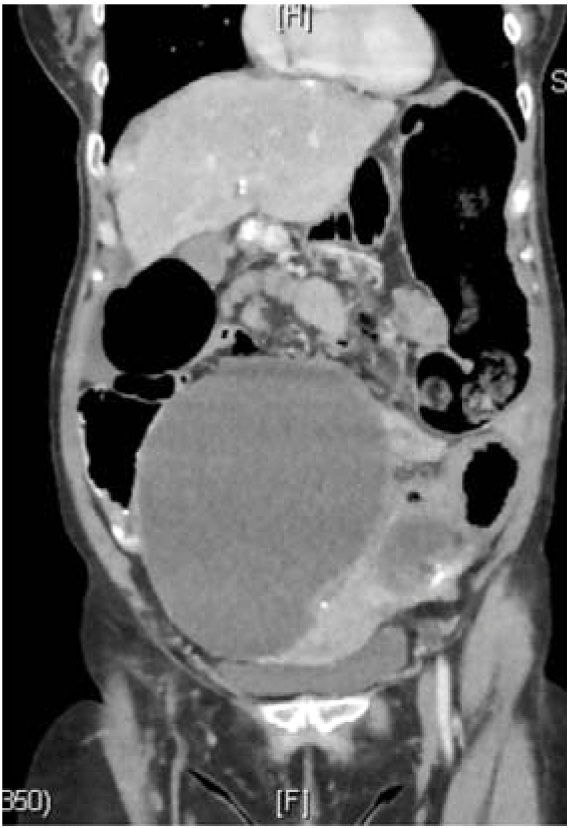

A 58-year-old female with no significant PMH, presented to the ER with acute onset abdominal pain, nausea, vomiting and diarrhea for one day. Patient was in her usual state of health eating and drinking normally, when she started having diffuse abdominal pain. Initially thought it was “gas pain”, but progressed to 9/10 pain throughout the day. Her pain was also accompanied by nausea, multiple episodes of vomiting and diarrhea. A CT abdomen pelvis revealed large bilateral pelvic masses obstructing the colon and ureters (Figure 6 and 7). Soft tissue nodules and ascites also present. Findings were most concerning for peritoneal carcinomatosis (Figure 8 and 9).

Figure 6: CT scan abdomen and pelvis. Large bilateral pelvic masses.

Figure 7: CT scan abdomen and pelvis coronal view. Large bilateral pelvic masses obstructing the colon and ureters.